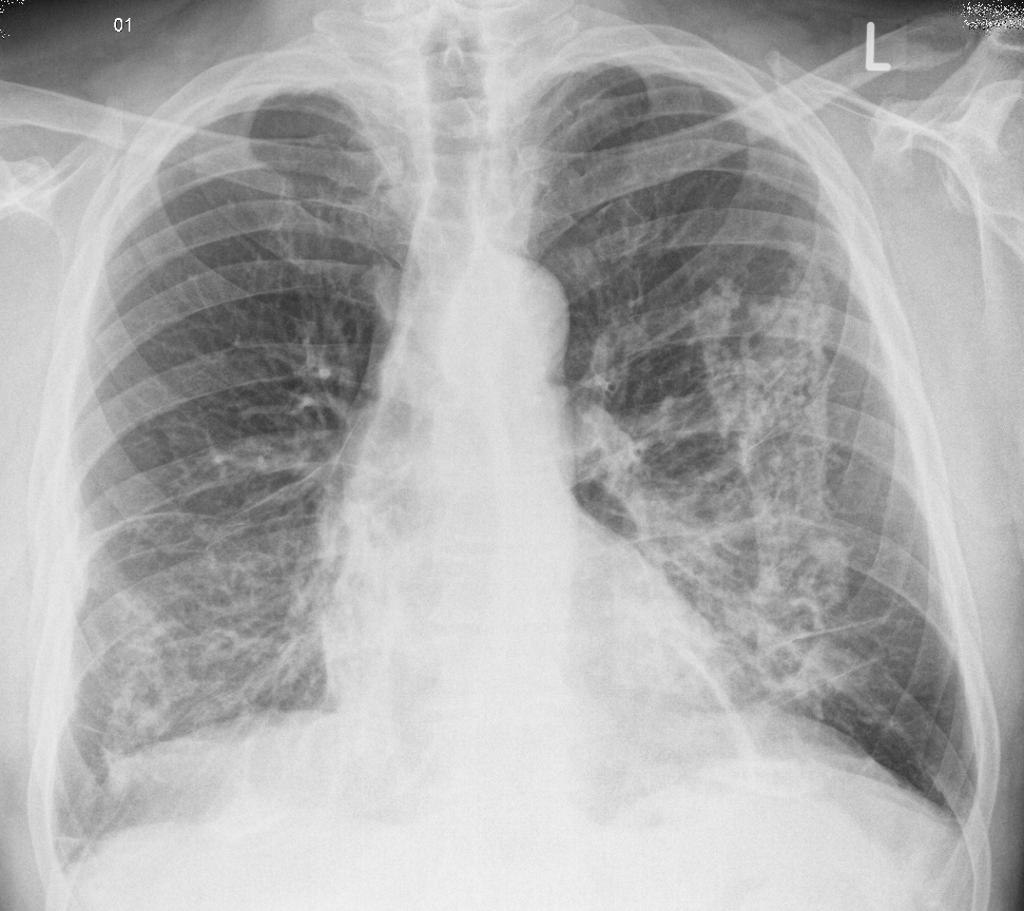

- Chụp X-quang hoặc CT ngực nhằm phát hiện các nốt phổi, khối u trong phổi và bệnh mô kẽ.